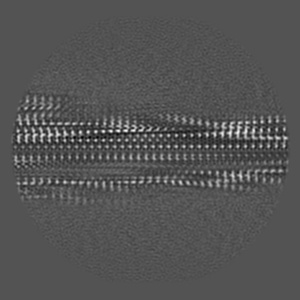

Cryo-EM structure of alpha-synuclein singlet filament from Juvenile-onset synucleinopathy

Helical reconstruction2.0 Å

Sample: Alpha-synuclein singlet filament extracted from the human brain with JOS